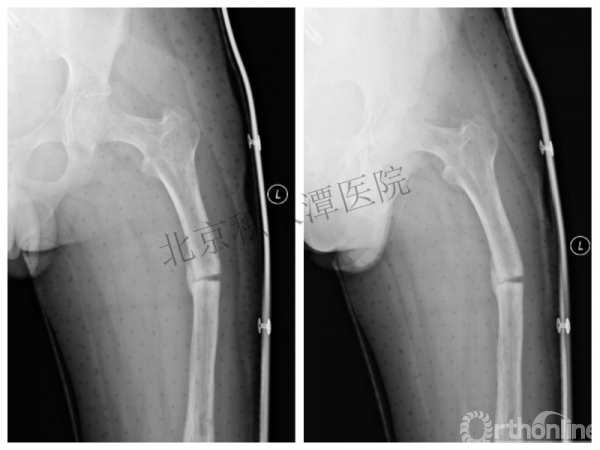

男孩 、5岁,初次骨折于2007年7月。

术后2年→再骨折→再次手术

钢板固定后一年

取板后再骨折→TEN

TEN取出后2个月

闭合复位再固定加尾帽

又过了4年!时间来到2015年

一年以后顺利愈合,实则危机四伏

数月后再骨折!牵引!

髋人字支具

外固定架术后一年

整整11年!是否治疗终结?